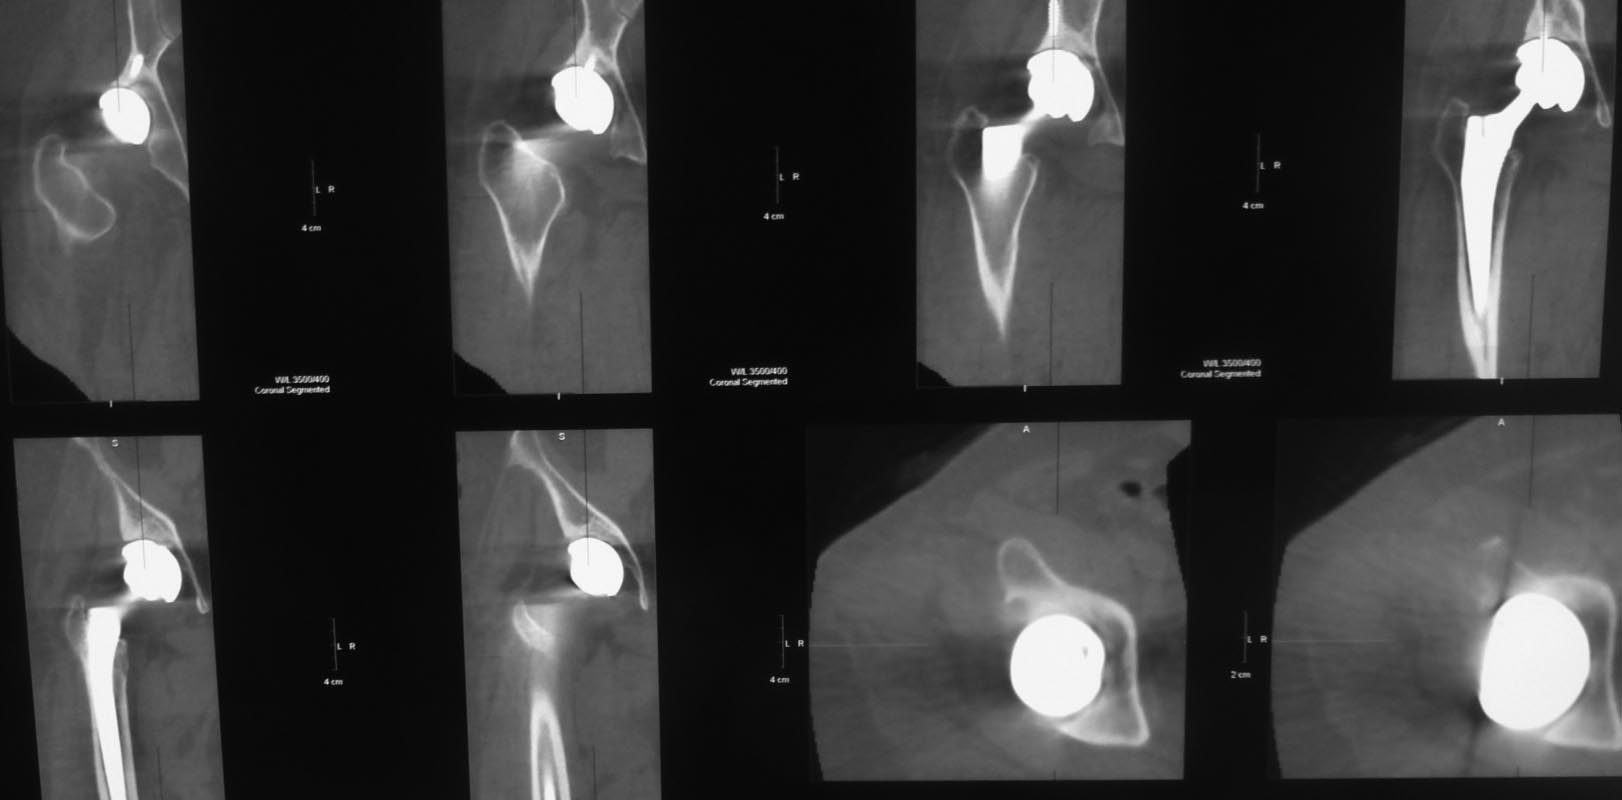

Пациент 58 лет оперирован 10 лет назад по поводу вывиха правого бедра с переломом головки. Во время открытого вправления был поврежден седалищный нерв (ягодичный доступ), по поводу чего впоследствии выполнены 3 вмешательства с неполным положительным эффектом. Через несколько месяцев после открытого вправления было осуществлено тотальное эндопротезирование.

Сейчас больше всего беспокоит стартовая боль, ходит с тростью, опираясь на нее 2 руками, ежедневно принимает нимесулид, хотя пытается убедить себя и окружающих, что, кроме стартовых, других болей нет. Резко ограничены движения в правом тазобедренном суставе, попытка ротации болезненна до крика. У невролога был - неврологическая патология отвергнута. Анализы крови нормальные, лихорадки нет. Казалось бы имеются все признаки нестабильности тазового компонента эндопротеза.

Вопрос: возможна ли нестабильность без рентгенологических признаков разрежения костной ткани вокруг винтов?

Уважаемый Сергей, у пациента имеются и клинические и рентгенологические признаки нестабильности чашки. Отсутствие резорбции вокруг винтов не должно Вас смущать. Ревизионное вмешательство однозначно показано.

Скорее всего нужно говорить о нестабильности вертлужного компонента. Есть разряжение вокруг чашки, которая скорее всего держится за счет винтов. Реэндоротезирование с заменой вертлужного компонента. Но перед операцией добиться получения пунктата на бакпосев, лучше даже 2 или 3 раза. Если есть инфекция то двухэтапное реэндопротезирование с применением цементного спейсора.

если винты сломаны на уровне чашки

Можно было начать с обычной рентгенограммы таза и простым анализом крови. Вместо КТ срезов, нужна прямая рентгенограмма таза, которая позволит сравнить уровень суставов и увидеть расшатывание вокруг ацетабулярного, а также бедренного компонентов. Сфокусированные КТ срезы, особенно 3Д не позволяют распознать вовлечение на уровне бедра и оценить артропластику в целом!

Спасибо за развернутый ответ. Но по поводу данного больного я задал единственный конкретный интересующий меня вопрос: возможна ли нестабильность вертлужного компонента при отсутствии признаков нестабильности фиксирующих чашку винтов? И именно для возможности ответить на этот вопрос представлены 3D срезы, позволяющие точнее оценить расположение винтов.К сожалению, на интересующий меня вопрос вы не ответили. А про результаты обычных анализов крови я написал, они в пределах нормы. И обычные рентгенограммы таза с захватом обеих ног пациенту сделаны. К ним у меня нет вопросов.